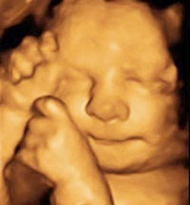

Ecografies obstètriques 3D i 4D

D’altra banda, a Noumèdic Figueres realitzem

ecografies obstètriques 3D i 4D.

Aquestes ecografies són d’alta resolució.

A més, permeten veure el nadó en temps real.